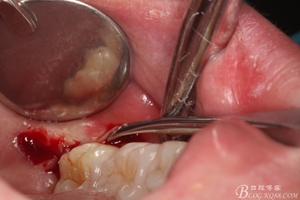

圖10. 翻開瓣。38牙冠還有部分骨質(zhì)覆蓋,遂用高速牙鉆去骨

圖11.去骨---暴露出38的牙冠最大周徑